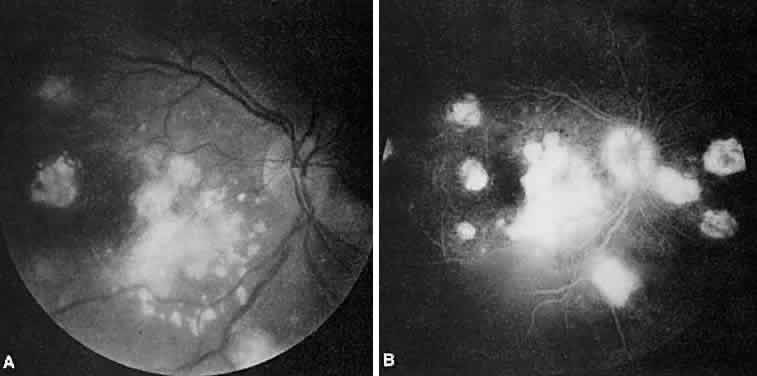

Vogt-Koyanagi-Harada syndrome, also known as uveomeningoencephalitis syndrome, is a systemic disease often found in young, darkly pigmented whites, blacks, native Indians, Hispanics, and Asians. It presents as an anterior and posterior uveitis with disc hyperemia, disc edema, and exudative retinal detachment (Figs. 2A and B and 3A). Systemic signs and symptoms include headache, hearing loss, poliosis, vitiligo, nuchal rigidity, seizures, and even coma. SRNV and disciform scars are late complications. The differential diagnosis should include AMPPPE and sympathetic ophthalmia.

Fig. 2. Vogt-Koyanagi-Harada syndrome. (A) Fundus photograph of the right eye and (B) the left eye showing bullous retinal detachments. (C) Fluorescein angiogram showing multiple hyperfluorescent leaks at the level of the retinal pigment epithelium. (D) Multiple coalescing leaks and fluorescein staining of the subretinal fluid. Large areas of hyperfluorescence involving the entire right posterior pole due to pooling of dye beneath the subretinal space.

Fig. 3. Vogt-Koyanagi-Harada syndrome. A. Fundus photograph of the left eye showing multifocal serous retinal detachment. B. Late fluorescein angiogram showing pooling of dye in the areas of serous detachment. C. Indocyanine angiography showing areas of blocked fluorescence corresponding to serous detachment. More areas of hypofluorescence are noted than those observed on fluorescein angiogram.

There is a characteristic fluorescein angiographic appearance in the early phase showing multiple discrete hyperfluorescent dots at the retinal pigment epithelial level that enlarge over time (see Fig. 2C and D). In the late phase, if there is a serous detachment, the fluorescein pools beneath the subretinal space (see Fig. 3B). The edematous disc hyperfluoresces in the late phase. Generally, the retinal vessels are unaffected.7,8 Retinochoroidal anastomoses also have been documented by fluorescein angiography.9

ICG angiography shows multiple hypofluorescent spots in the posterior pole (see Fig. 3C). These spots may coalesce and obscure the filling of large choroidal vessels. When serous retinal detachment develops, the marked hyperfluorescence observed on FA is not as prominently noted in ICG angiography, presumably because of the highly protein-bound nature of ICG. In fact, diffuse late hypofluorescence may be observed in patients with serous retinal detachment.10 Ill-defined areas of hyperfluorescence corresponding to diffuse choroidal staining may be seen in some cases in the late phases of the angiogram. The optic disc may stain with ICG in the acute phase but usually is minimal compared to that observed on FA.